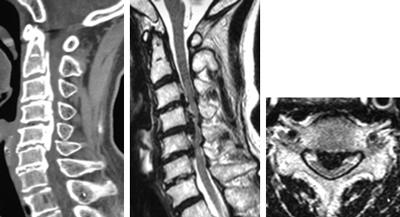

後縦靱帯骨化症、黄色靱帯骨化症

どんな病気?

せぼね(脊椎)は7個の頚椎、12個の胸椎、5個の腰椎と仙椎から構成されます。腰椎は主に5つの骨と、間にあるクッションのような椎間板、また神経組織が通っている脊柱管から成り立っています。後縦靱帯骨化症は椎体の後面で脊髄の前にある後縦靱帯が骨化する病気で、黄色靭帯骨化症は脊髄の後ろにある黄色靭帯が骨化する病気で、頚椎が最も発症頻度が高いですが、胸椎や腰椎にも起こり得ます。いずれも根本的な治療法がないことから、厚生労働省難治性疾患克服研究事業の対象疾患に指定されています。白人に比べて東アジアや日本人に多く、頚椎後縦靱帯骨化症は本邦で約3%、男女比はおおよそ2:1ですが、全身性の骨化では女性に多いことが知られています。家族内発症もあることから遺伝的関与の可能性、そのほか肥満や糖尿病との関連も指摘されています。

症状

後縦靱帯の骨化や黄色靭帯の骨化があるからといって、必ずしも神経障害が出るわけではありません。但し、骨化のタイプや大きさによっては、発症や進行をしやすいことがあり、特に転倒による急激な悪化には注意が必要です。局所の症状として、頚部や背部の痛み、また肩こりなどの症状が生じます。脊髄が障害されると、手指の巧緻運動障害(箸が持ちづらい、字が書きづらい、ボタンが上手くはめられない)、痙性歩行(ふらつき・つまずきやすい・歩行がぎこちない)、膀胱直腸障害(頻尿・残尿感)などの症状が生じます。

検査方法

骨化のタイプや大きさ、不安定性の有無、脊髄の圧迫具合、またせぼね全体のバランスなどを見るためにX線検査やCT検査、MRI検査などを行います。進行例では脊柱管の狭さをより詳しく評価するために入院して脊髄造影検査を行う場合があります。成人期では血管性のしびれがないか評価するために両手足の血圧を測ったり、骨粗鬆症の有無を評価するために骨密度検査を行うこともあります。

治療方法

肥満や糖尿病がある方は、減量や糖尿病のコントロールをお勧めします。頚部痛などの局所症状に対しては、鎮痛薬やビタミン製剤などの内服、カラー、リハビリテーションなどの保存治療で経過をみます。保存治療で十分な効果が得られない場合、あるいは手足の力が入りづらい(麻痺)、歩行が不安定、また排尿や排便に障害(膀胱直腸障害)がある場合などには手術治療を考慮します。重度の脊髄障害は、不可逆的になり回復が困難となることがあるため、早急な外科的治療を要することがあります。

後縦靭帯骨化症・黄色靭帯骨化症に対する低侵襲手術には以下の種類があります。

脊椎腫瘍

脊椎腫瘍はいわゆる脊椎(せぼね)にできる腫瘍です。原発性脊椎腫瘍と転移性脊椎腫瘍(がんなどの転移)に分類されます。原発性脊椎腫瘍は種類も豊富で若い方からお年寄りの方までの幅広い年齢層にみられますが、頻度は高くありません。転移性脊椎腫瘍は、中・高齢者に多い傾向にあります。肺がん、乳がん、前立腺がん、胃がん、甲状腺がん、腎細胞がんなどが頻度の高い原発巣です。発生部位により頚椎、胸椎、腰椎、仙骨腫瘍に分類されます。

-

甲状腺がんの第5頚椎転移の症例

脊椎腫瘍に対する治療は様々ですが、原因となっている腫瘍に対する治療が最も重要となります。従って、原因となる腫瘍を治療する主科と整形外科との密接な連携が重要となります。近年では分子標的薬や免疫チェックポイント阻害薬等の薬により、これまで良い治療成績を得るまた、ことが困難であった腫瘍に対しても、長期の予後が期待できるようになって来ています。その中で、脊椎への転移は麻痺や疼痛のために生活の質を著しく悪化させる可能性がある疾患です。そこで、脊椎への転移への治療は原因となっている腫瘍に対する十分は治療の継続を前提としながら、放射線治療や骨修飾薬の組み合わせが中心となります。しかし、脊椎の骨破壊が著しく、脊椎の不安性性により疼痛が強い場合や、脊髄を腫瘍が圧迫する(または可能性が高い)場合には手術を行い、術後にその他の治療を組み合わせて治療を進めていく場合があります。